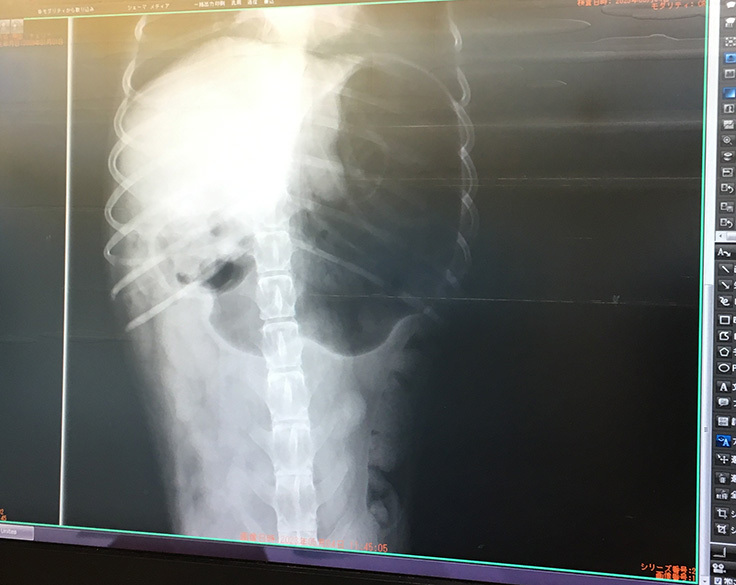

レントゲンを撮ったら、やはりガスが溜まっているそうです。

「注射器ではガスが抜けない肋骨の部分の胃にガスが溜まっているので、チューブでガスを抜くようにしましょう」と先生に言われました。